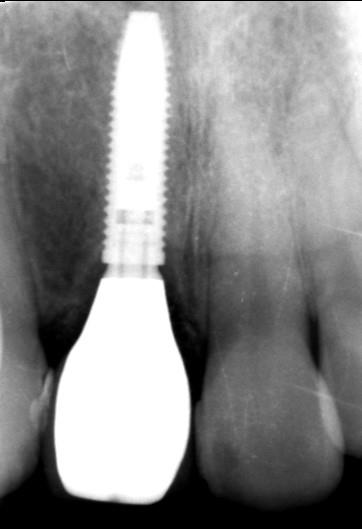

術後 レントゲン

| 主訴 | 前歯の差し歯が折れてしまい、腫れて痛みがある。できるだけ隣の歯を傷つけずに治したい。 |

|---|---|

| 年代・性別 | 30代 男性 |

| 治療部位 | 上顎左側 1 |

| 治療費用 | インプラント手術料 300,000円 |

| 手術回数 | 1回 |

| 治療期間 | 6ヶ月 |

| 手術時間 | 90分 |

| 治療回数 | 4回 |